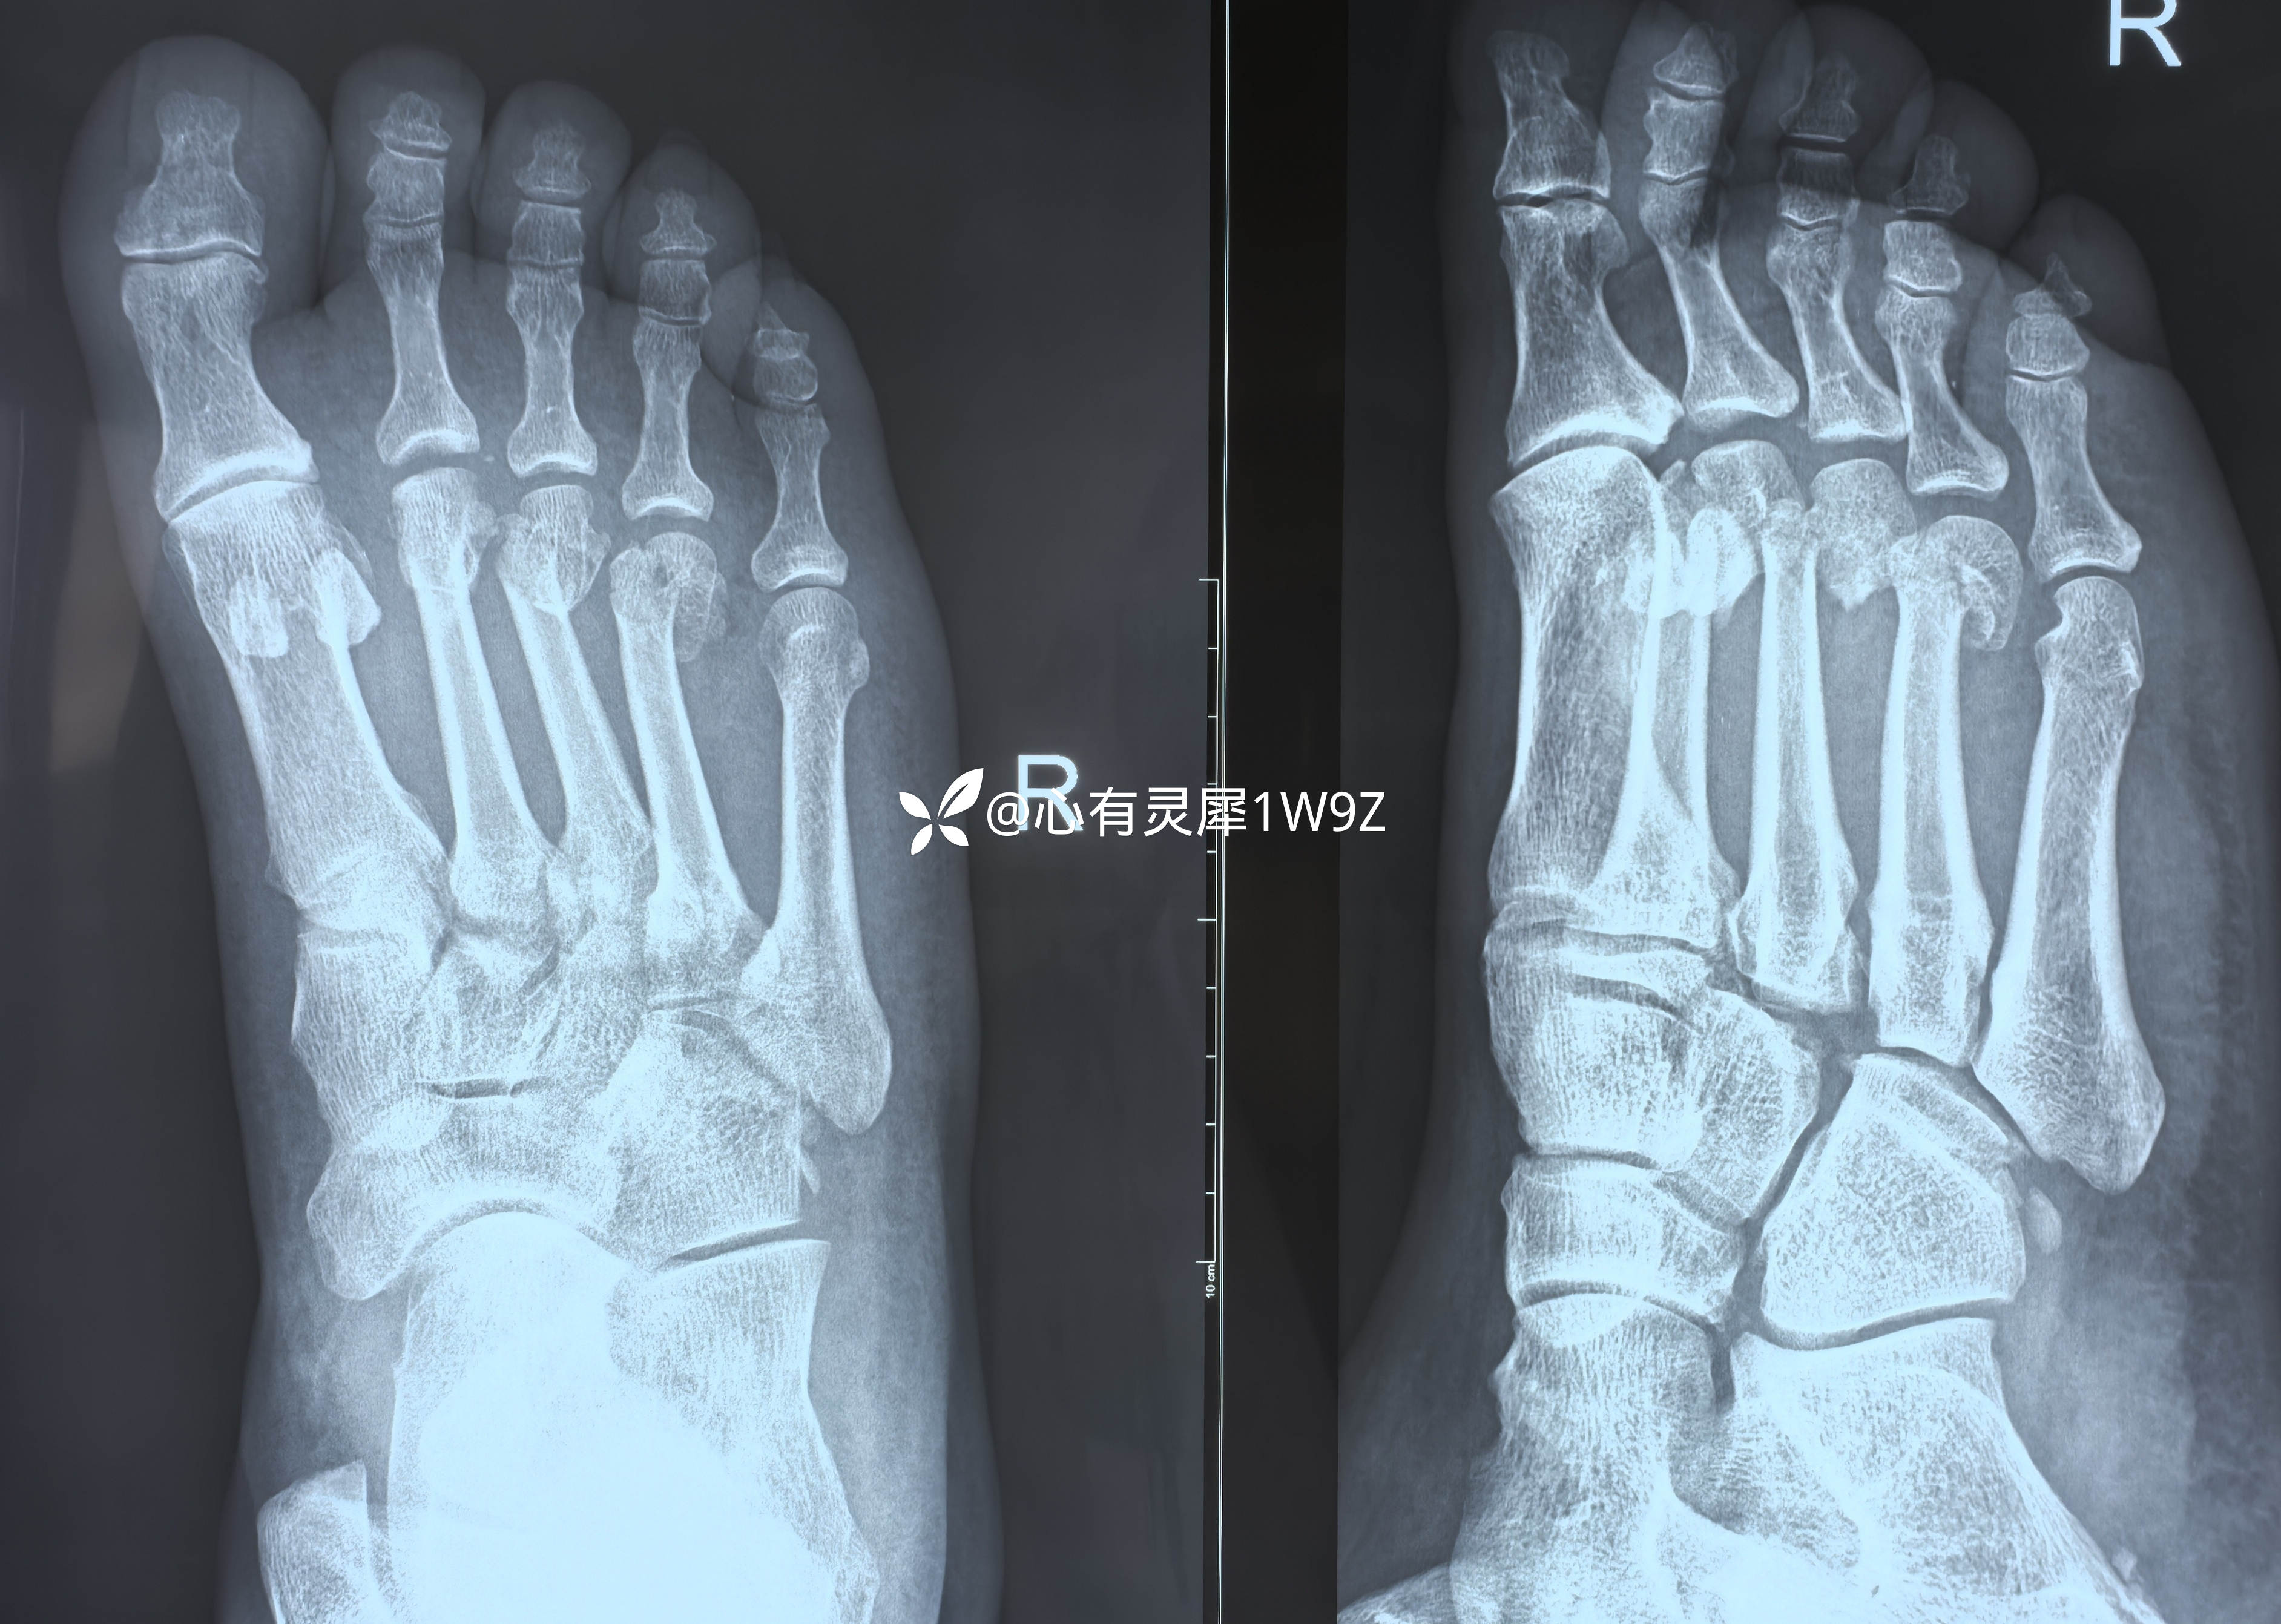

跖骨头骨折

【患者信息】:男性58岁

【主诉】:右足砸伤一天入院。

【临床诊断】:右足第234跖骨远端骨折

【治疗经过及结果】:计划用这种方式固定,手术还没做,请教一下有关细节。

请教一下各位老师同事,计划做克氏针髓内固定,一般用多粗的克氏针?从跖骨近端向远端固定是用电钻钻入还是徒手钻入?